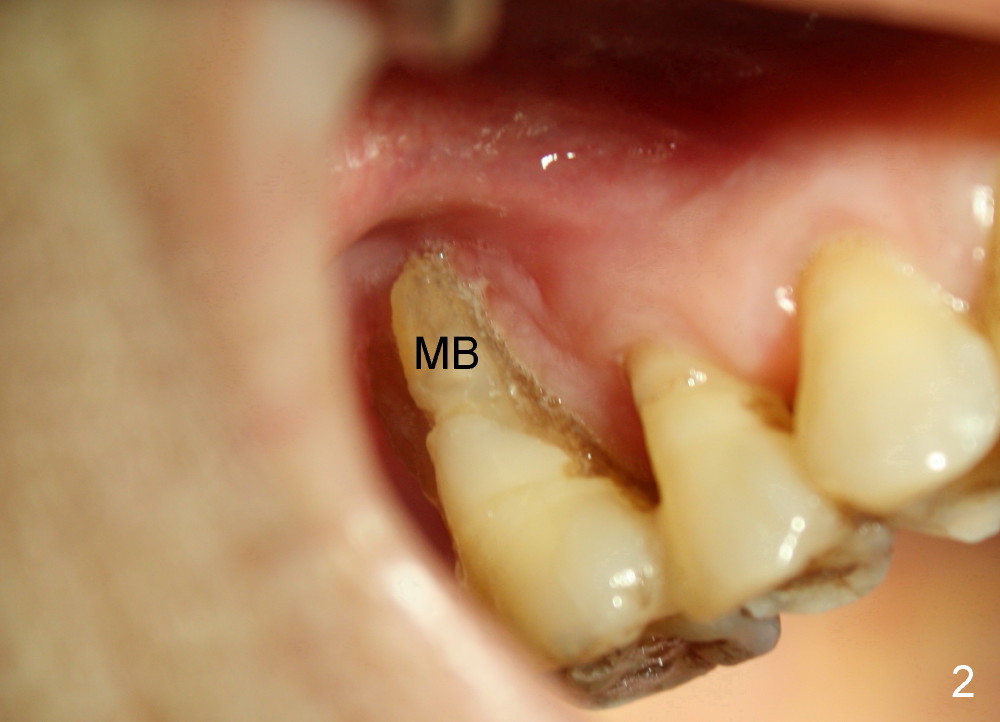

A 68-year-old lady presents to clinic with chief complaint of upper right pain. The tooth #3 has advanced periodontitis, compounded by occlusal trauma (Fig.1). There is severe bone loss, especially around the buccal roots, MB and DB. The latter are exposed (Fig.2,3).